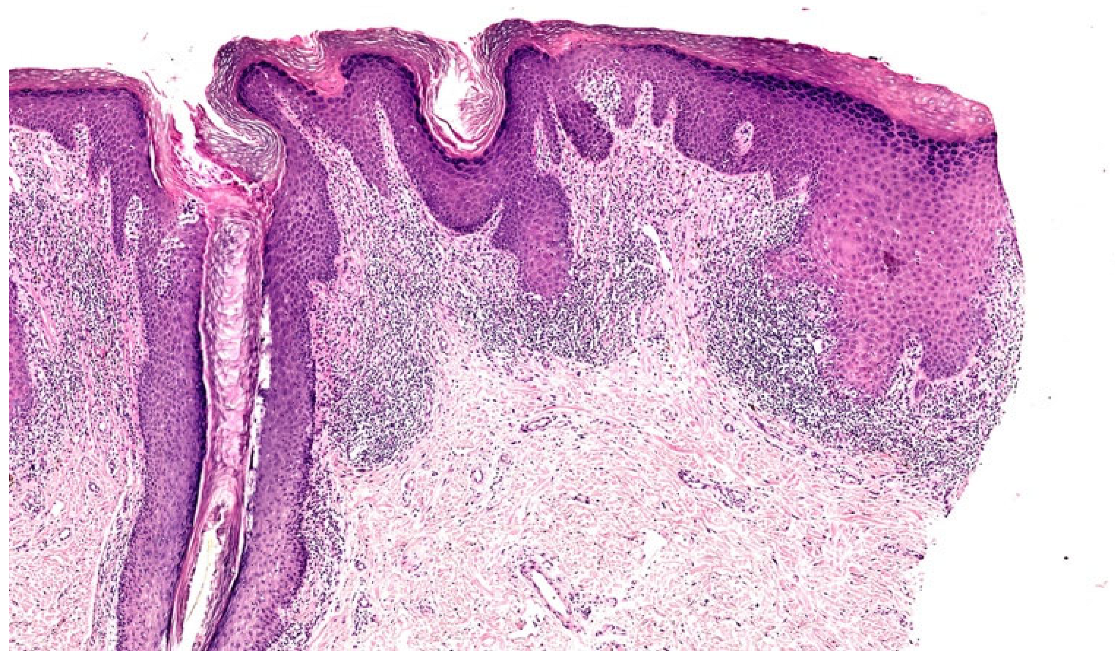

3.2.6. Lupus Erythematosus/Lichen Planus (LE/LP) Overlap Syndrome

| LE/LP overlap | Painful, bluish-red or hypopigmented plaque acquiring a verrucous (wart-like) appearance | Wedge/not wadge-shaped | Focal hyperplasia, parakeratosis, and laminated orthokeratosis | Irregular, thin | Presently, with significant perifollicular and perivascular inflammatory cell infiltrate | Vacuolar alteration at the DEJ, thick basal cell layer PAS positive | Variable |